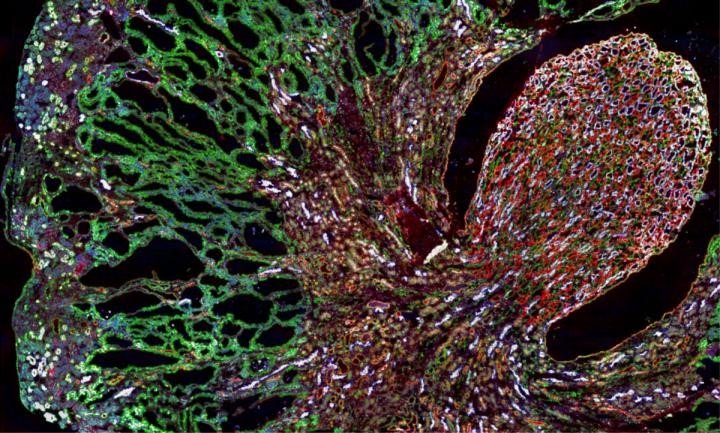

Misfolded MUC1-fs protein (green) builds up in the kidneys of a mouse model of MUC1 kidney disease.

The mutation results in the production of a truncated, misfolded protein dubbed MUC1-fs that collects in patients’ kidney cells. As MUC1-fs accumulates, kidney cells die, eventually leading to kidney failure.

Experiments in human kidney cells, an MKD mouse model, and patient-derived kidney organoids showed that the cargo receptor traps MUC1-fs. This keeps the misfolded protein from reaching the lysosome (an organelle whose job is to chew up unwanted proteins), causing MUC1-fs to rise to dangerous levels in kidney cells.